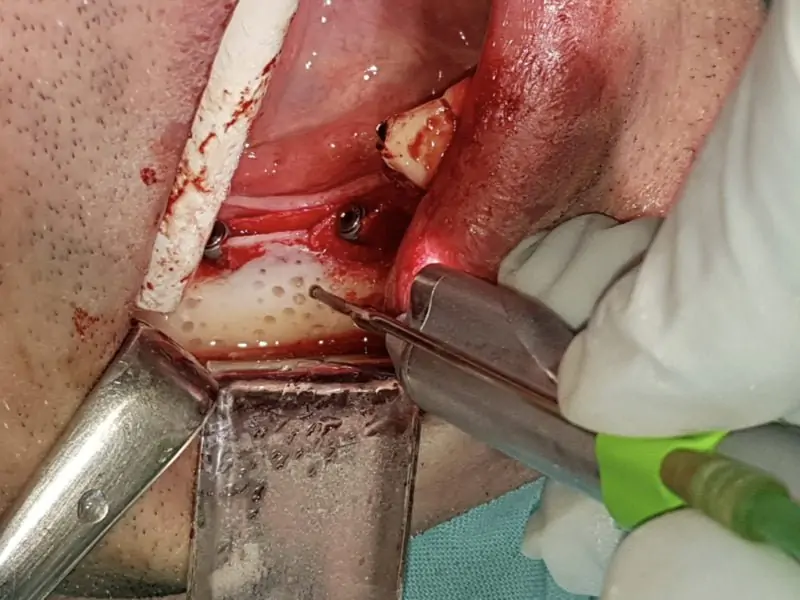

This is the case presenting crest split with immediate insertion of two 3P implants by BB dental along with bone augmentation with artificial bone Novocor plus, platelet rich fibrin, and resorbable membrane by BB Dental. The crest of lower jaw was less then 2mm wide and it was neccessary to split the bone using piezo surgery, mallet and chisel. In this way we were able to gain enough of bone width to place two implants both 3.5/10.

After the insertion of implants with good primary stability, we used PRF in combination with artificial bone Novocor plus to create “sticky bone” which is essential for new bone growth. This augmented implant site was covered with PRF membranes and then with BB dental collagene membrane. Prior to augmentation bone was drilled with roung burr in other to get blood vascularization. The flap was sutured with monofilament suture which is essential in proper wound healing.